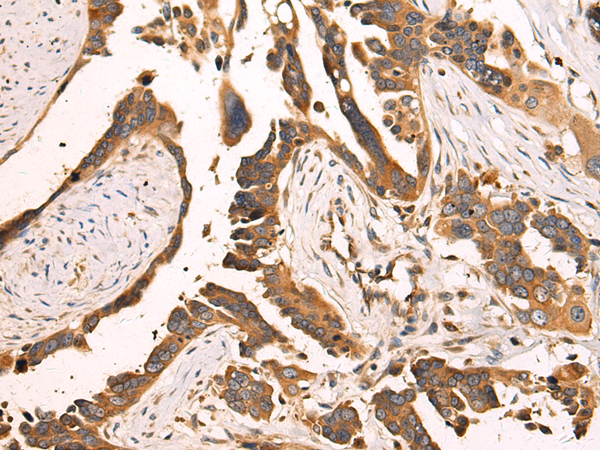

ELISA, IHC |

IHC positive control: |

Human colorectal cancer |

IHC Recommend dilution: |

100-200 |